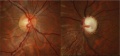

Fundoscopic photos demonstrating significant cup-to-disc asymmetry with severe optic disc cupping of the affected left eye in a patient with CEU. Photos courtesy of Leonard Seibold, MD.